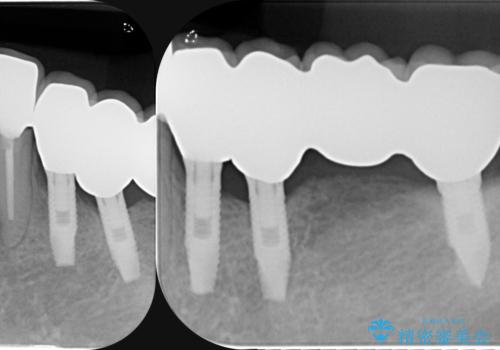

虫歯による歯の喪失 インプラントによる咬合機能回復

- 深い虫歯や歯の破折、多数の問題を口腔内に抱えて来院されました。

虫歯の徹底的な除去、安定した噛み合わせを達成するインプラント治療、深い虫歯、根管治療といった複数の治療項目を一つづつ積み重ね、長期的な予後を目指します。

複雑な問題点に対する明確な治療目標を立てることで、最終的に長い予後を期待できる治療を達成することができます。